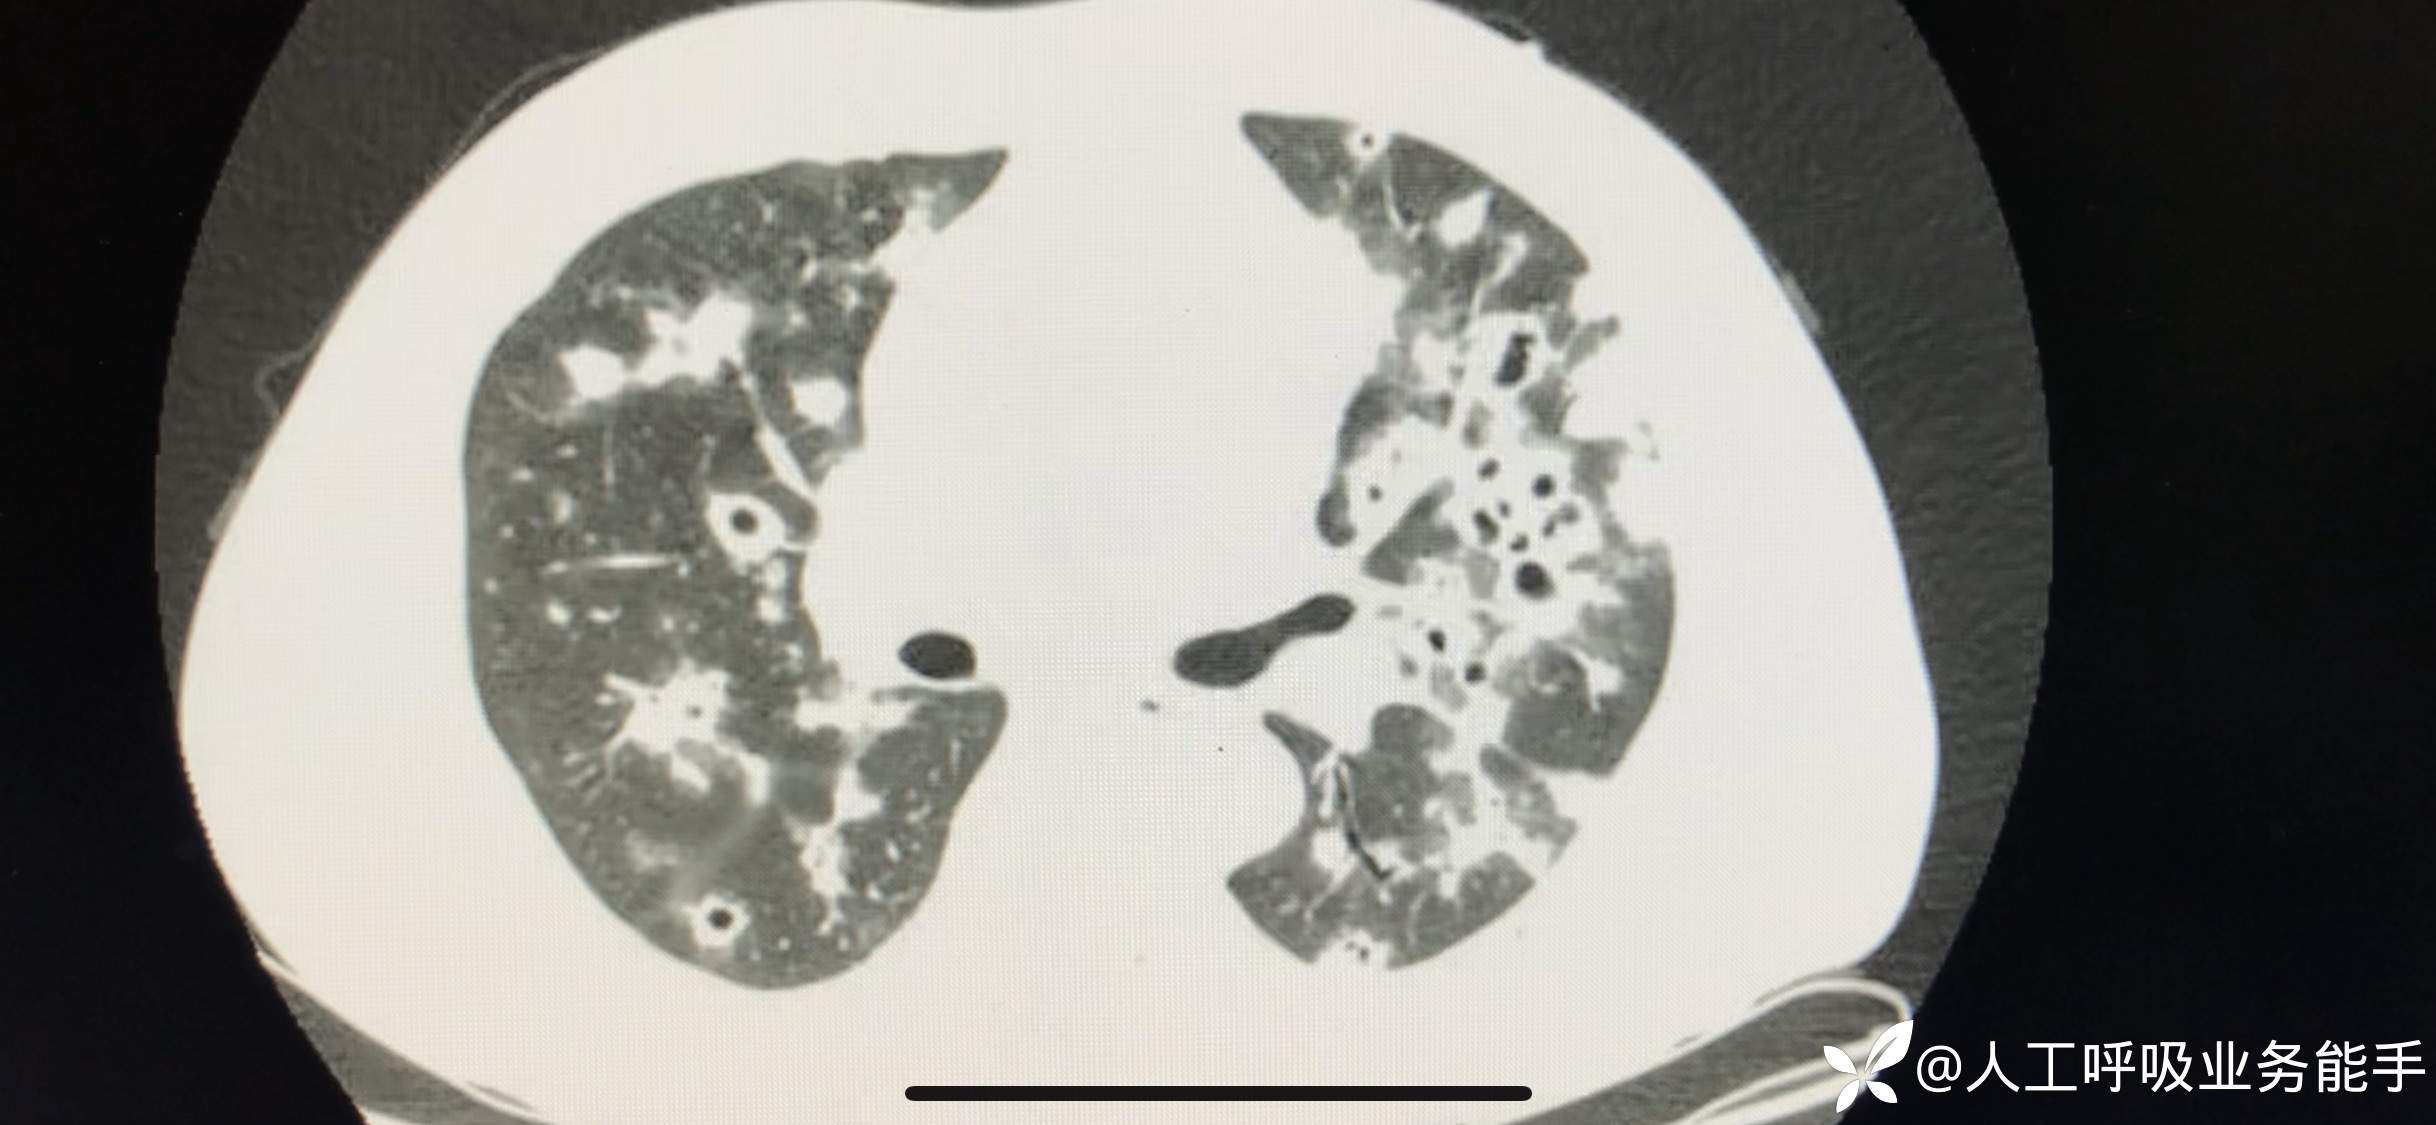

初诊影像: